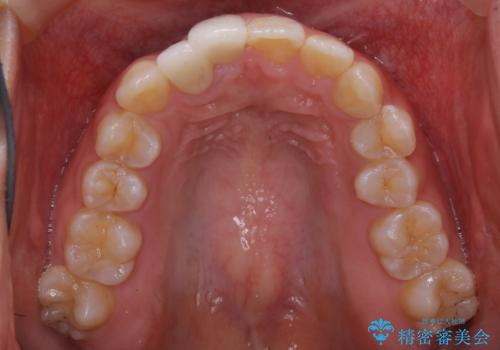

右下の隙間を閉じるため、歯の数を合わせるため、右上の小臼歯を一本抜歯しています。

以前の治療はいわゆるセラミック矯正と呼ばれるものになります。

歯の生え方が悪い歯をセラミックだけで治療しようとした場合、どうしても自然な美しい歯を作ることはできません。

また、無理な治療により神経をとらなければならなかったり、磨きにくくなってしまうことで虫歯ができてしまったりと、歯の寿命を縮めてしまう恐れがあります。